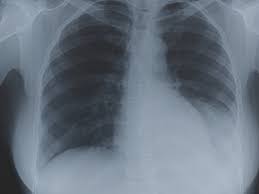

Chest X Ray To Check Fitness Is Outdated Health Gulf News

Chest X Ray To Check Fitness Is Outdated Health Gulf News from gulfnews.com